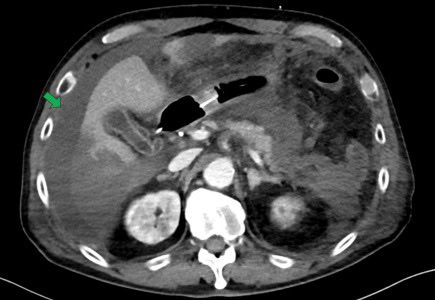

Sin embargo, al tercer día de ingreso, la paracentesis reveló un hallazgo inusual: líquido ascítico de color negro, con elevación significativa de amilasa y bilirrubina.

FIGURA 3: Líquido ascítico negro. Foto: Caso Clínico - Kobori et al.

La coloración oscura del líquido, aunque rara, podría atribuirse a la presencia de productos de degradación hemorrágica y enzimas pancreáticas en un contexto de necrosis tisular masiva.